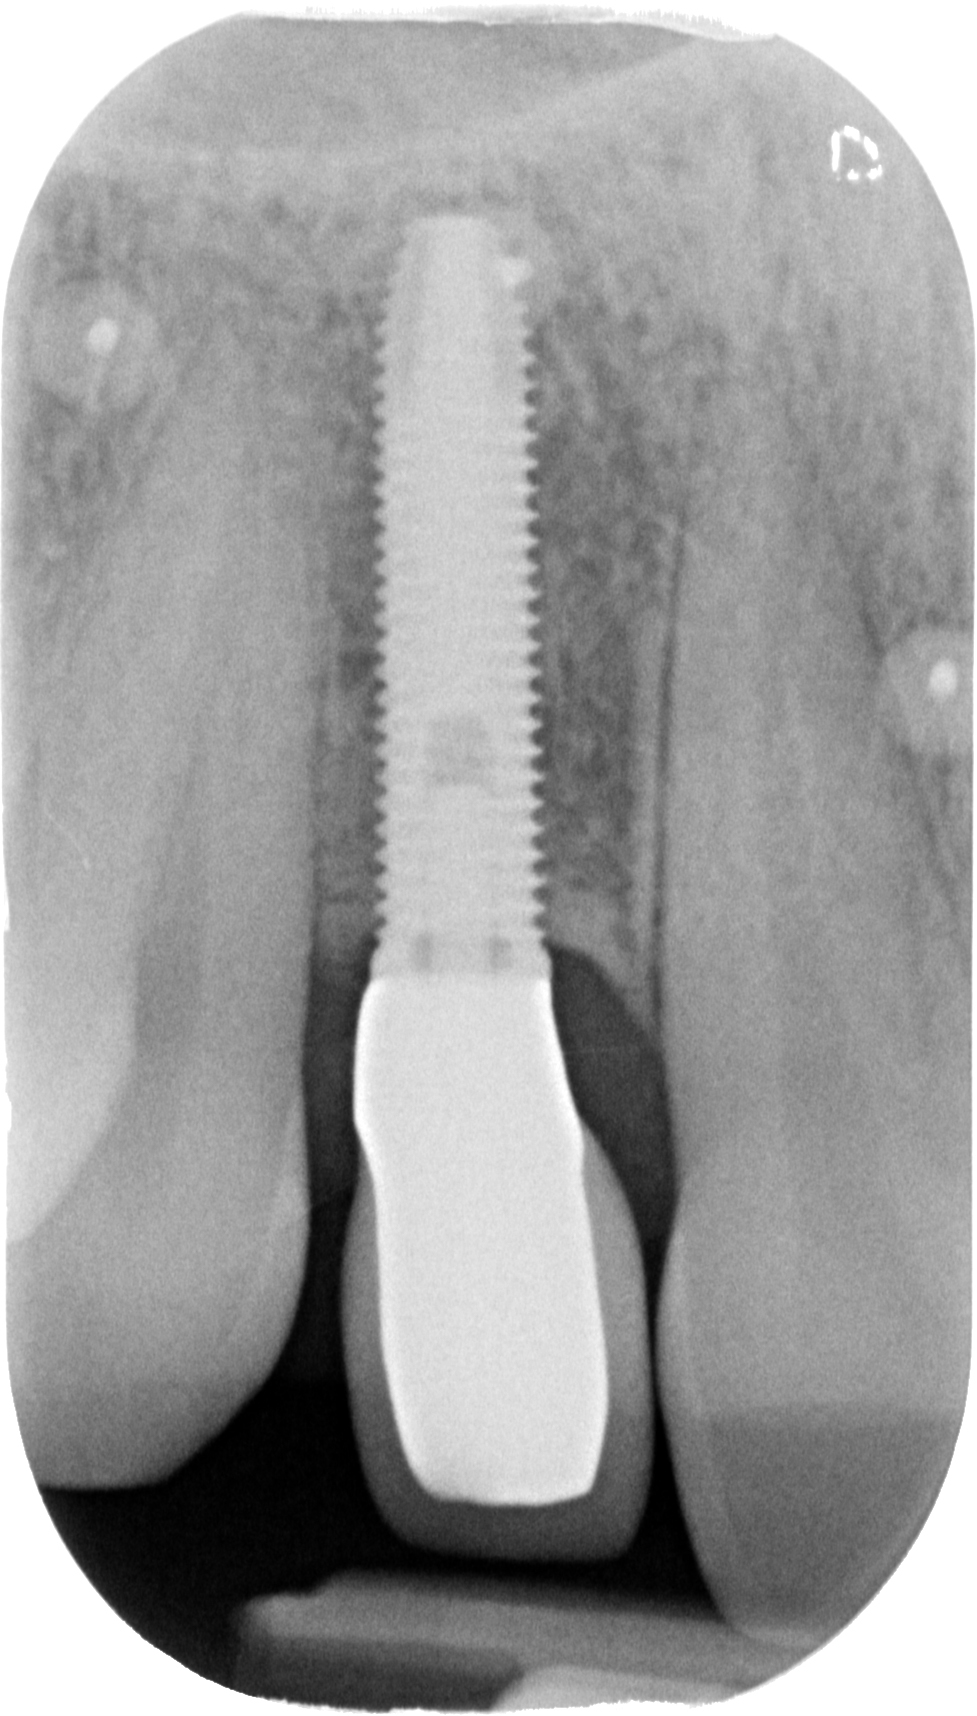

Come credi che si possa risolvere un caso come questo…

DSC_6241

o come questo…

Sconosciuto-X-20151123-200312-XYHMH6ZQBS2X-4

senza tecniche di chirurgia avanzata?

Attenzione a non confondere: ho detto avanzata. Non invasiva.